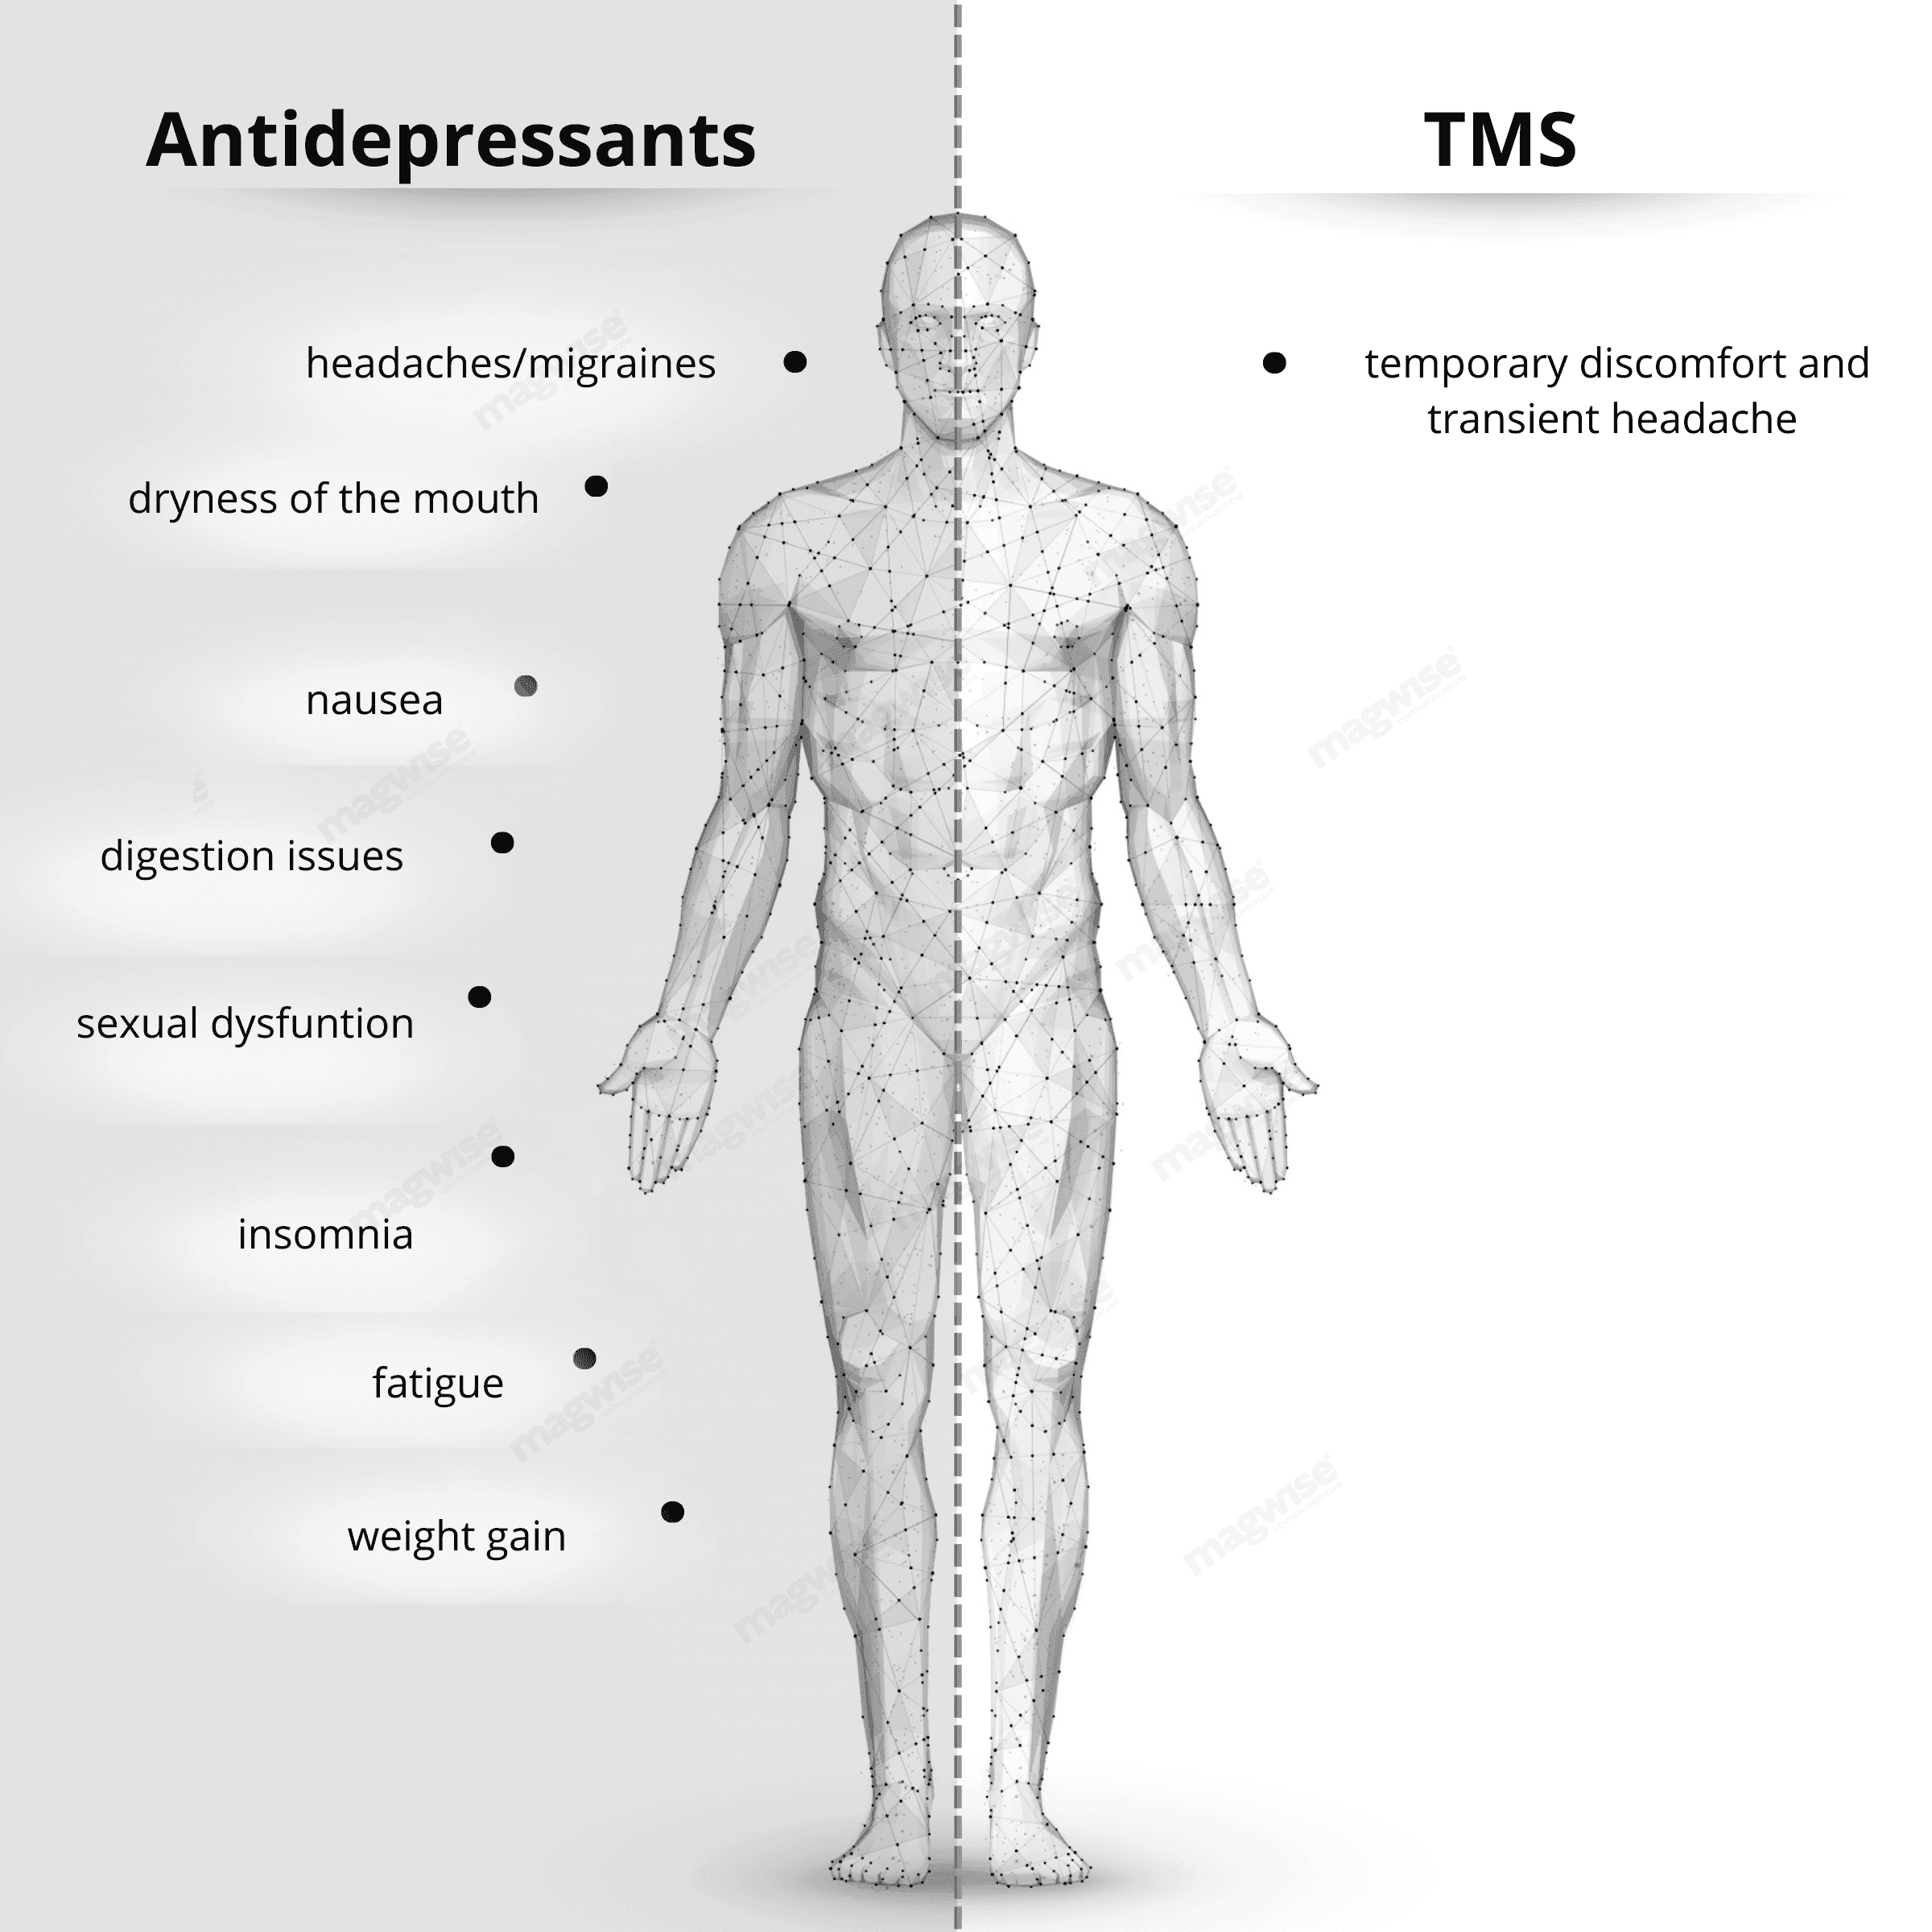

- An alternative to medication

TMS can be used as a stand-alone treatment or as an adjunct to medication, helping to reduce the need for drugs and their side effects.